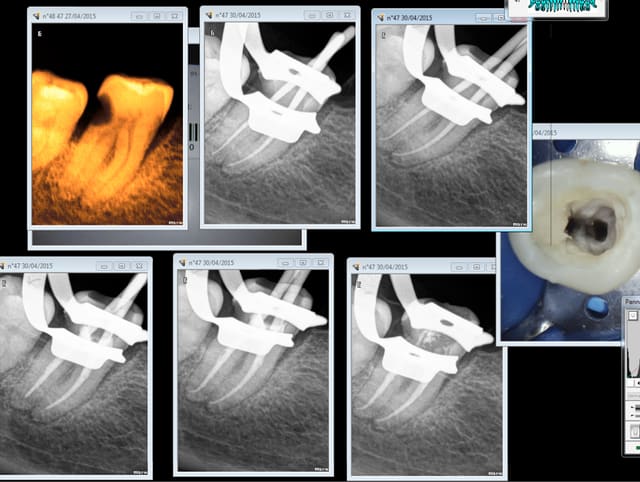

Toc, toc ca t'énerve les endos ? -)))))

Eh oui des fois il faut s'y reprendre à plusieurs fois, radio cone en place ( fois 2), radio cone scellé en place (fois 2) radio après mac spadden. ouf !

Merde ,encore une abusive, j'aurais du faire un coiffage à la biodentine.

Tiens casa pour te faire plaisir. 1 mm de r25 pété sur cette 27. Quand on réutilise le matos censé ne servir qu'une fois pour cause de paiement au lance pierre du donneur d'ordre voilà ce qui arrive ( j'avais pourtant pris mes précautions (cathétérisme) sur cette dent de rhinocéros ultra longue)

Quelqu'un connait un endo exclusif pour aller chercher le morceau pété ? -))))